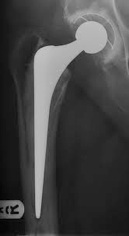

The x-rays below show what cemented, un-cemented and hybrid hip replacements look like.You can also see how the surgeon can measure the patients leg length post operatively on the hybrid x-ray.

UN-CEMENTED:

The Corail/Pinnacle un-cemented hip replacement is the most successful un-cemented hip system in Europe. It was designed 25 years ago. The implant is coated with hydroxyapetite(synthetic bone) and the patient’s bone grows onto the implant over time. When we exercise this results in micro-fractures to our bones. This is normal and our bone repairs itself. This is why our bone becomes thicker and stronger when we exercise more. One of the potential advantages of un-cemented implants is the ability for this process to continue to ensure good fixation of the implant. This process does not occur with cemented implants and as a result in younger active patients cemented implants can loosen and require revision.